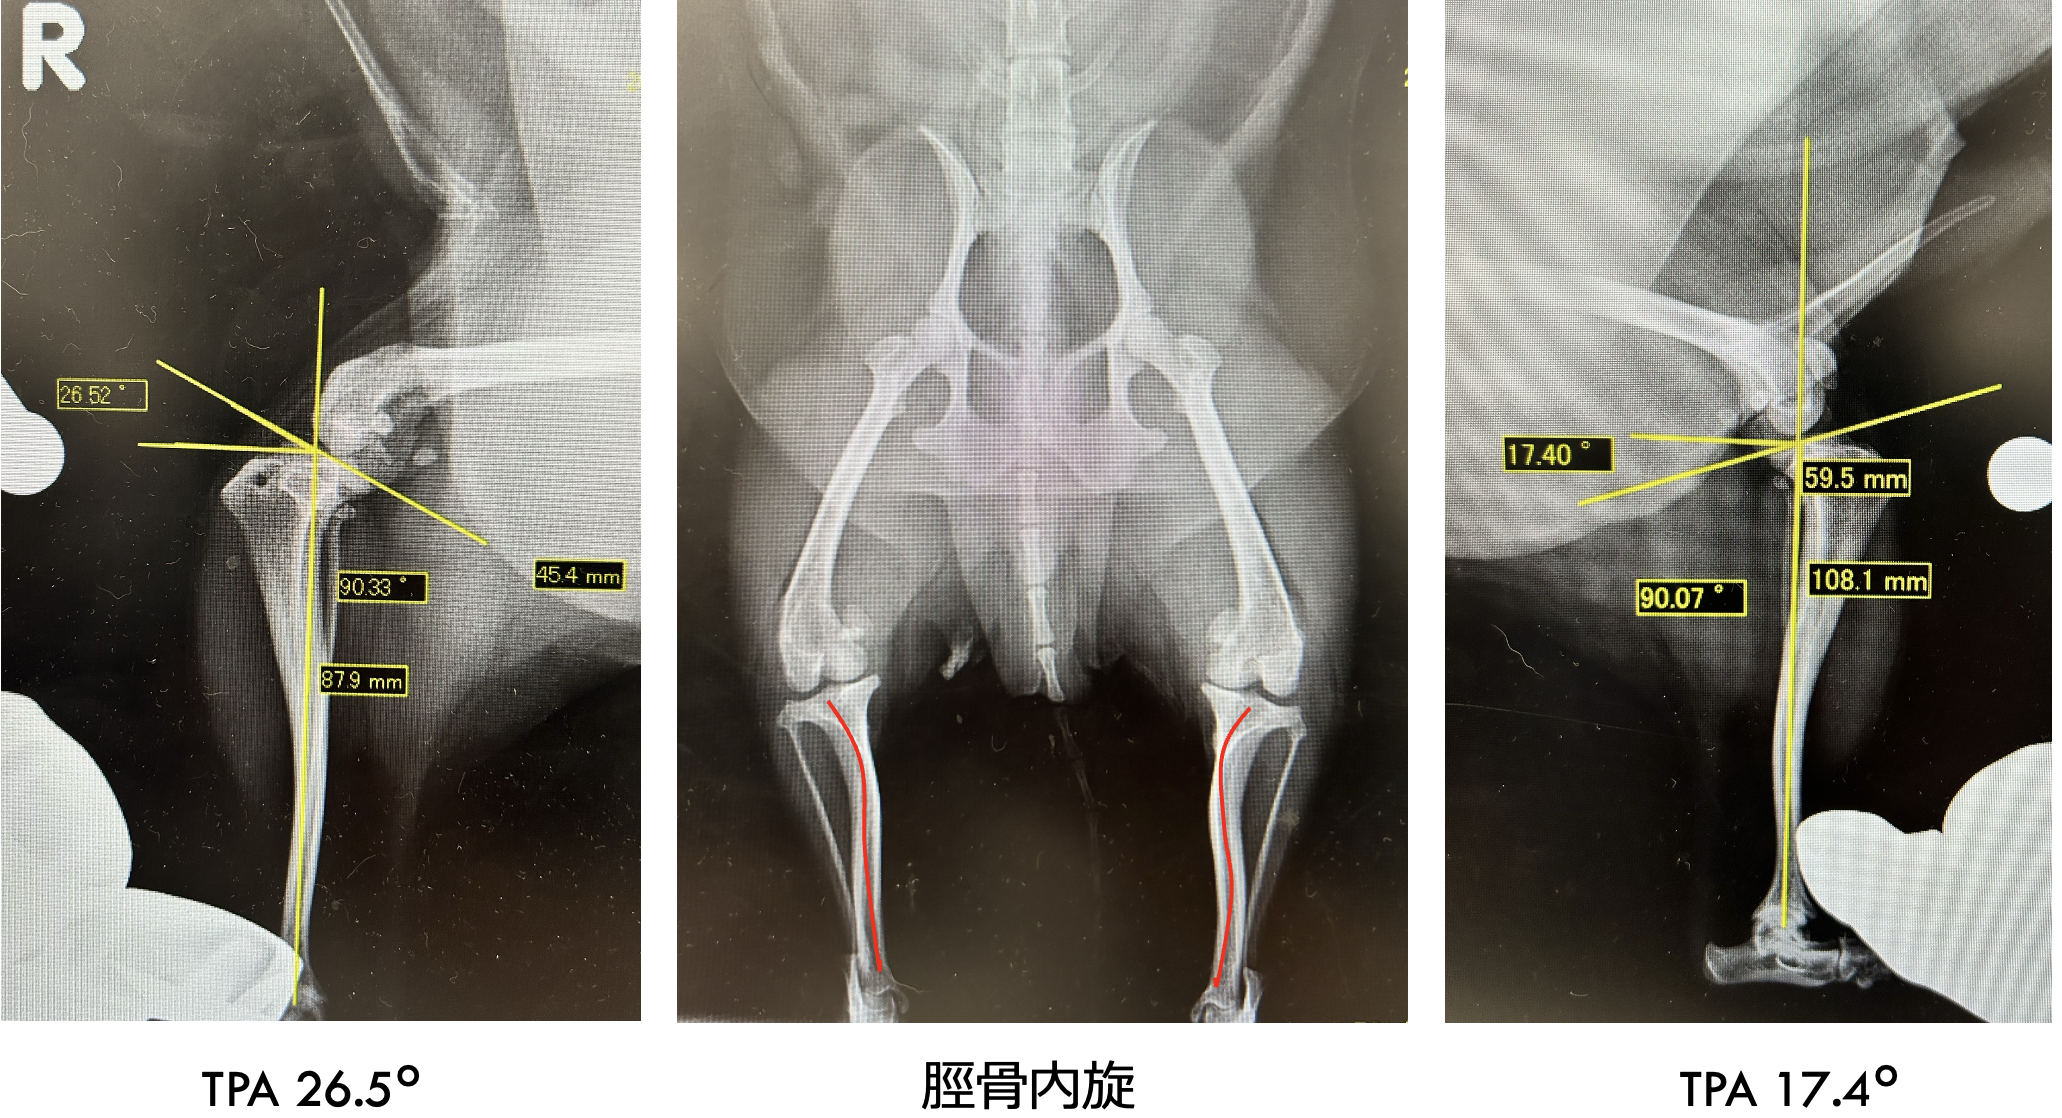

触診より両側パテラ内方脱臼G4 、レントゲンより右TPA26.5°、超音波検査より滑車低形成・前十字靭帯不明瞭

左右膝蓋骨内方脱臼、右前十字靭帯断裂

before